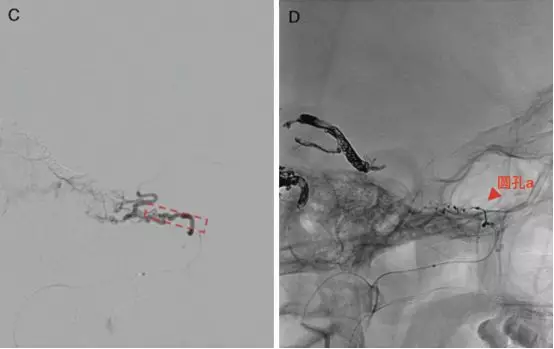

A-B,左侧颈外动脉的侧位和正位。迂曲的脑膜中动脉(直箭)和圆孔动脉(箭头),均供应畸形血管团(Levitt 2011)。

C,圆孔动脉超选造影侧位。虚线的四边形表示左侧三叉神经V2支的大致位置。

D,栓塞后颈外动脉造影侧位,圆孔动脉(箭头)完全栓塞(Levitt 2011)。

E,Onyx栓塞后左侧颈外动脉造影,未见圆孔动脉显影。F,术后CT显示栓塞的圆孔动脉(箭头)以及圆孔动脉与颅底的关系(Levitt 2011)。

三叉神经分支的动脉血供(Levitt 2011)。V2(星号)由圆孔动脉供血(直箭),V3由脑膜副动脉(空箭)供血。注意圆孔动脉内超选的微导管,以及该动脉特征性迂曲走行。还可见翼管动脉,经翼管走向破裂孔。